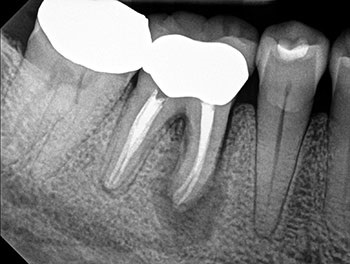

Case 10: Failing ‘well done’ NSRCT

This patient’s teeth #30 and #31 were treated by an endodontist. The endodontist found all the canals, achieved patency and shaped and filled each canal to length. When the periradicular tissues surrounding both teeth failed to heal, the endodontist recommended extracting both teeth because of VRFs. By then, tooth #31 developed a J-shaped lesion, suggestive of a VRF. Nothing suggested that tooth #30 had a VRF, other than that it was a “good-looking” or “well-done” NSRCT that failed. Yet both were recommended for extraction.

The somewhat skeptical patient came to see if these teeth really needed to be extracted. Nonsurgical retreatment was recommended. The patient didn’t want to lose his teeth, but he also didn’t want to pay to re-treat teeth that could not be saved.

Tooth #31—the tooth that was more likely to be fractured—was addressed first. To maximize the likelihood of healing, this tooth was treated in multiple visits using a calcium hydroxide intracanal medicament and obturated after bony healing was complete. The patient was delighted that his tooth had been saved, but also somewhat perplexed that the original endodontist gave up on a tooth that could have been saved. He has now scheduled re-treatment for tooth #30.

More than a few cases have been seen for second opinions after a dentist completed RCT on a tooth that failed shortly after, then told the patient to extract the tooth because it must be cracked because the NSRCT “looked perfect” radiographically. Although shaping and obturation can be judged radiographically, the most important factor—disinfection—cannot.

Fig.40: Postop PA.

Fig.41: Recall PA.

Fig.42: Recall CBCT.